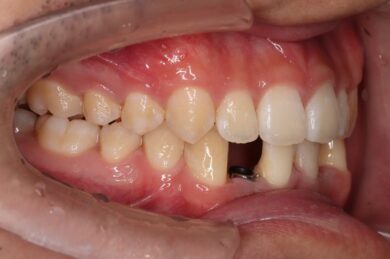

下顎の前歯は通常6本ですが、中央から2番目の歯(側切歯)が左右2本とも欠損している先天性欠如の患者様です。

初めにマウスピース矯正「インビザライン」による術前矯正を11か月行いました。各隙間を寄せ、インプラントを埋入するスペースを確保し、適切な咬合関係を確立します。

インビザラインの治療計画では、下顎前歯がより美しく審美的に並ぶよう、ご自身の歯とインプラントの歯がほぼ同じ幅径になるよう計算し配列を行いました。

インプラントは世界シェアNo,1の「ストローマン」インプラントを採用。若年者の方も安心して長期的にお使いできるよう配慮しています。